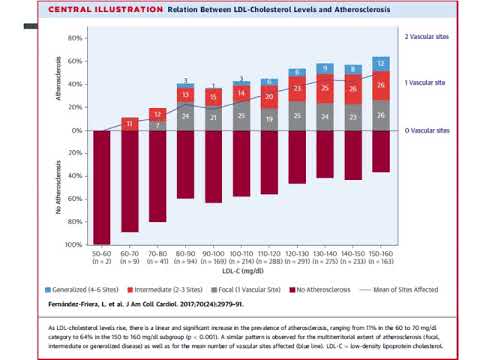

Valores normales de colesterol LDL y ateroesclerosis subclinica. Residencia de Cardiología. Hospital C. Argerich. Buenos Aires